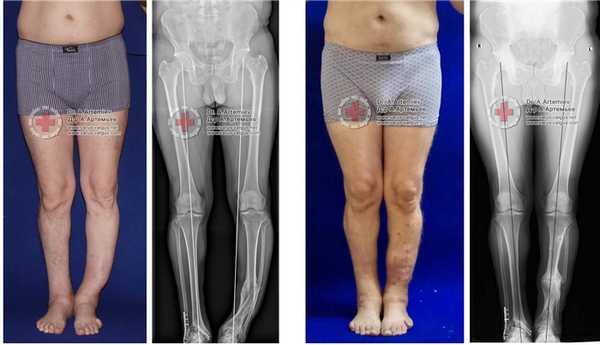

Часто встречающаяся ситуация - вальгусная деформация ног + наружная ротация + укорочение левого бедра 2 см. Слева деформация более выражена, поскольку деформированы были и бедро, и голень. Провели двухэтапную коррекцию. 1 этап - левое бедро, 2 этап - обе голени. Genu valgum (в отличие от genu varum) часто обусловлена деформацией бедренных костей. Поэтому для определения объема операции обязательно нужен рентген ног по всей длине.

Достаточно грубая варусная деформация у девушки 25 лет исправленная при помощи метода Илизарова. У аппаратной методики есть важное преимущество, она позволяет производить коррекцию в любых плоскостях, одновременное увеличение длины, и одновременно проводить вмешательство на обеих нижних конечностях. Аппарат Илизарова можно спрятать под свободными брюками, и ходить без трости или костылей. Подобная операция не только является профилактикой развития в последующем гонартроза с поражением внутренних отделов коленных суставов, но так же значительно влияет на эстетику нижних конечностей, что крайне важно, когда мы говорим о девушках.

Ещё один клинический пример, одновременного исправления угловой, ротационной деформации и укорочения левой голени. Травма за 5 лет до операции в результате падения с 5 этажа, левая голень срослась с грубой варусной деформацией, удлинением и внутренней ротацией, правая нога укоротилась за счёт явлений посттравматического артроза голеностопного сустава. В итоге ноги получились вот такими. Обращало на себя внимание, что деформированная левая голень длиннее правой. При выпрямлении эта разница стала бы еще более заметной. В итоге решили укоротить левую голень и выпрямить её. Резецировали около 5 см берцовых костей и срастили их в прямом положении. Устранили варус и внутреннюю ротацию.